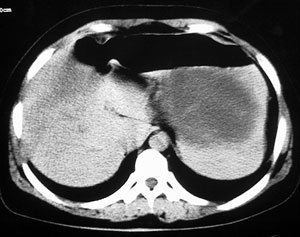

强化片

这个要问下病史,如无胰腺炎病史首先考虑胰腺体尾部的粘液囊腺瘤,此瘤太大,有分叶和实性成份要考虑恶性或潜在恶性可能,后两幅主动脉左旁结节状强化影止于左肾静脉,考虑双下腔静脉,请结合往下的片

应该增强扫描看看有没有壁结节,排除囊腺癌

胰腺囊腺瘤或囊腺癌.增强是必需的。

以下是引用守望可可西里在2006-8-30 10:57:00的发言:[br][br] 定位:胰腺体尾部。[br] 定性:胰腺囊腺癌可能性大。[br] 理由:胰腺体尾部呈多囊状分叶,部分病灶与前腹壁粘连,且下部形态不规则,毛糙不整、凸凹不平。囊壁厚薄不一致,多个大小不等壁结节突入,囊壁及壁结节明显不均匀强化。偏右侧囊内见液-液平面样相对高密度,呈与壁结节类似强化。性质:1.出血?2.壁结节?

以下是引用duguo在2006-8-30 12:13:00的发言:[br]支持胰腺囊腺癌诊断,建议穿刺活检.